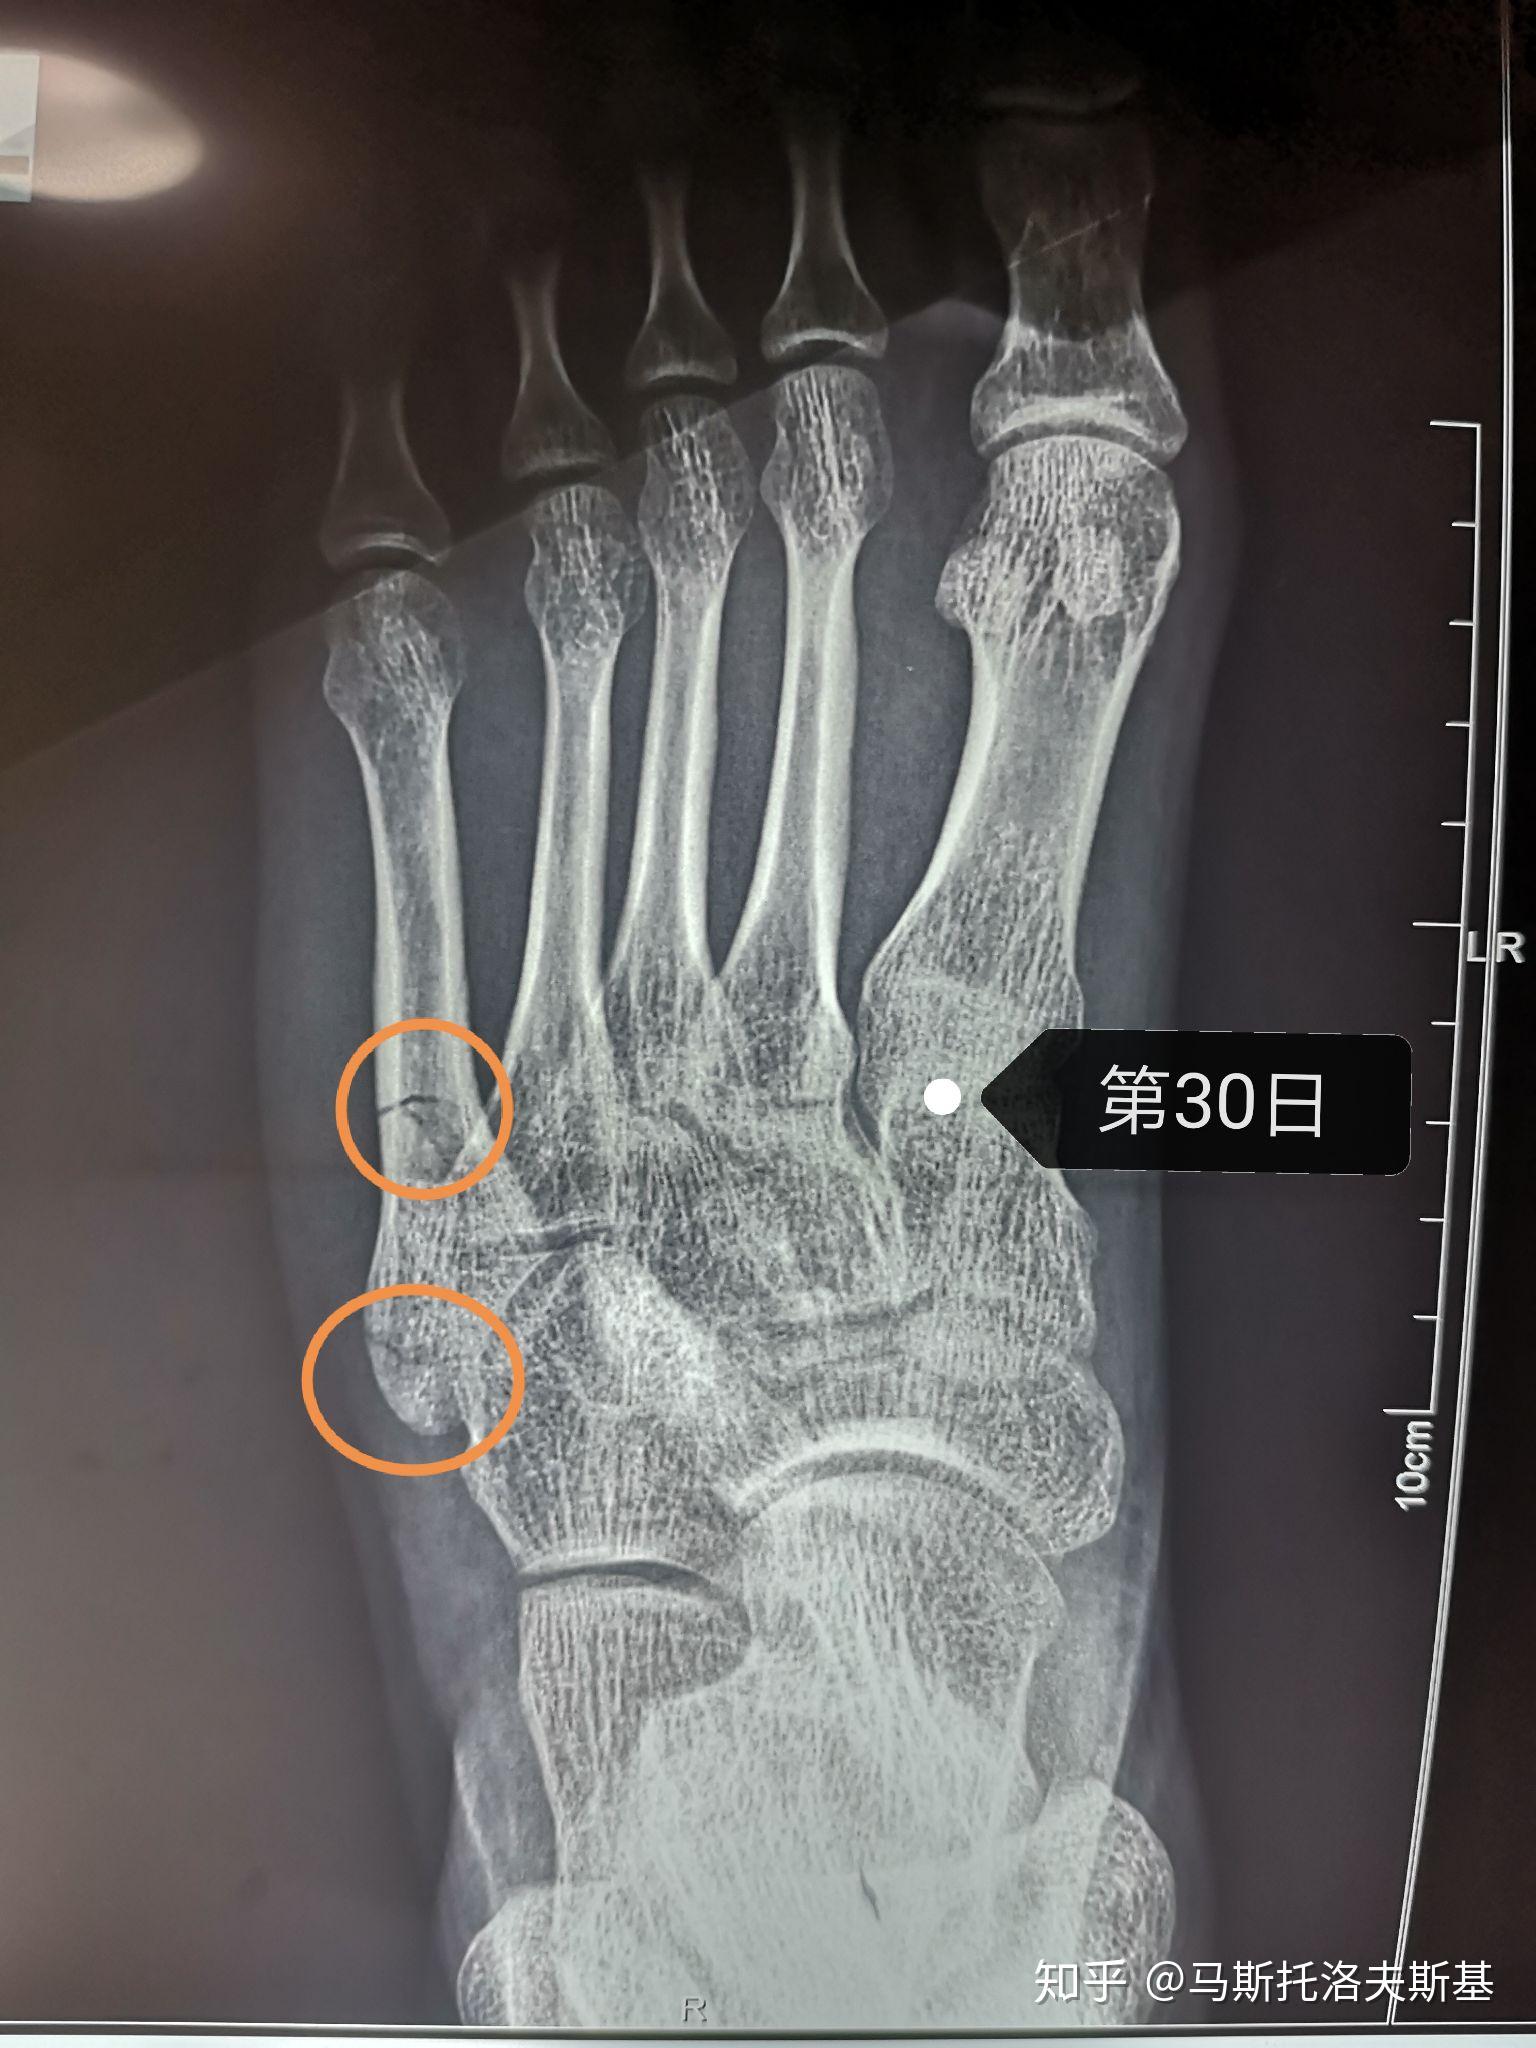

第五跖骨骨折1个月 从2月13到3.14,骨折30天了,满一个月了.